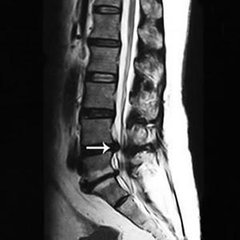

走不动路便是腰椎管狭窄的危害之一,也是较具代表性的症状。腰椎管狭窄多见于中老年,男性居多,多体现为慢性或复发性腰背痛有时伴有坐骨神经痛。腰过伸运动时痛苦加剧。痛苦继续数月致使数年进而出现典型的间歇性跛行。>>>有哪些方法能有效治疗椎骨狭窄?点击咨询在线专家

在久站或行走一段后因为腰椎伸直脊柱前凸,使神经根受压加剧或因神经细胞需氧量增加而呈相对缺氧情况,因而惹起下肢麻痹肌痉挛痛苦和跛行在歇息或折腰后,神经根受压和神经缺氧情况好转痛苦消逝。神经系统体征有下肢肌力削弱,肌肉萎缩,感觉反射反常和大小便功用妨碍。感觉妨碍出现一般迟于运动妨碍。>>>生活中有哪些方法能有效预防椎管狭窄的发生?点击了解